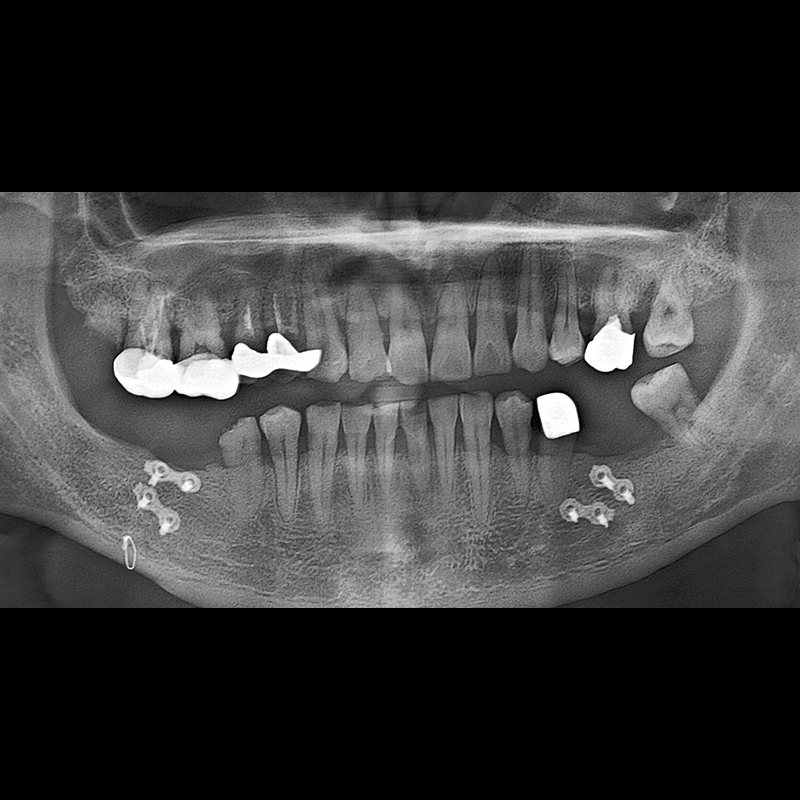

BEFORE AFTER

Implant before and after 2025.05.30

Implants were placed in the missing tooth and in the tooth position where it was difficult to save.